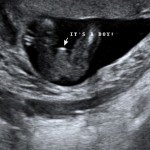

4D/5D/HD Ultrasound Gallery

Gallery